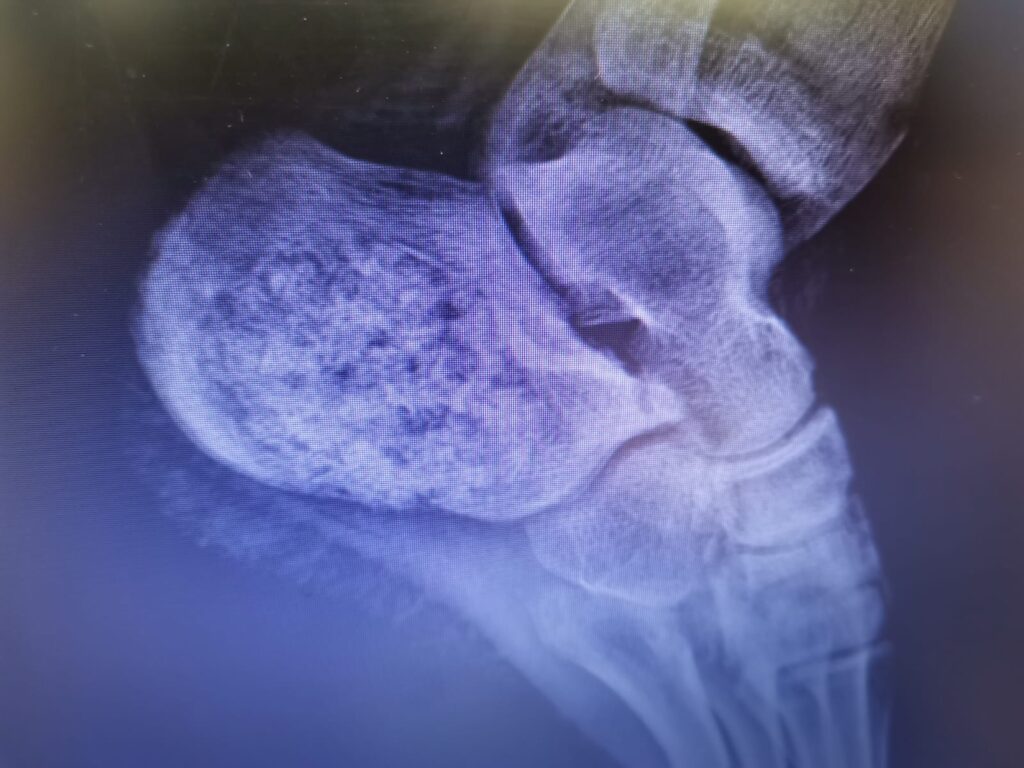

În urma cu aproximativ o lună, o pacientă de 20 de ani a fost diagnosticată clinic și imagistic, cu o formațiune tumorală osteolitică (schwannom sau neurinom) ce a cuprins aproape în totalitate osul calcaneu stâng.

„Cazul este deosebit deoarece abordează o patologie tumorală extrem de rară a țesutului osos cu un grad de distrucție osoasă importantă. Acest lucru a necesitat, în premieră, reconstrucția osoasă cu alogrefă osoasă umană a defectului osos restant după excizia țesutului tumoral. Intervenția chirurgicală a decurs în doi timpi, inițial practicându-se excizia marginală a tumorii, în urmă cu trei săptămâni, precum și efectuarea de către medicii anatomo-patologi, doctorul Andreea Botezan și doctorul Luminița Miron, a examenului histopatologic, ce a permis diagnosticarea rapidă a unui schwannom intraosos, o tumoră benigna a nervului periferic, excepțional localizată la acest nivel. Astfel în literatura de specialitate sunt citate numai 5 cazuri de acest fel. Etapa a doua chirurgicală, s-a desfășurat în ziua de 14 decembrie 2022, realizându-se reconstrucția calcaneului stâng prin umplerea defectului osos cu alogrefă osoasă umană, importată de la Banca de țesuturi Colentina București tot cu sprijinul domnului doctor Andrei Nica, medic coordonator al Băncii de Țesuturi, care este mereu alături de noi și îi mulțumim. Pacienta evoluează normal postoperator urmând a fi externată. Conduita de tratament ulterior implică o imobilizare a gleznei și piciorului stâng pentru o perioadă de 6 săptămâni, sprijinul pe piciorul stâng fiind amânat pentru o perioadă de 3 luni de la intervenție. Particularitatea acestui caz o reprezintă atât raritatea leziunii ca frecvență și determinare tisulară, dar și efortul echipei medicale de a diagnostica și trata în timp record, aproximativ 3 săptămâni, o leziune tumorală cu potențial de agravare rapidă și severă, care netratată în timp util ar fi produs colapsul osos prin fracturarea spontană a calcaneului, urmat de un deficit funcțional major, la o pacientă cu vârsta foarte tânără. De asemenea, trebuie de remarcat că este al doilea caz tratat, cel puțin relatat de literatura de specialitate, prin reconstrucție cu alogrefă osoasă umană de la banca de țesuturi, primul caz fiind raportat în 2016 de Centrul Oncologic Hunan din China. Celelalte trei cazuri au fost raportate în Turcia (2012), India (2012) și Brazilia (2020) dar cu defecte osoase mai mici, la două cazuri efectuându-se plombare cu autogrefă osoasa, de la același pacient, și într-un caz fixare cu șuruburi și plombarea defectului osos cu ciment acrilic”, a declarat doctorul Răzvan Codrin Bandac medic primar ortoped, șef secție Ortopedie a Spitalului Județean Suceava.